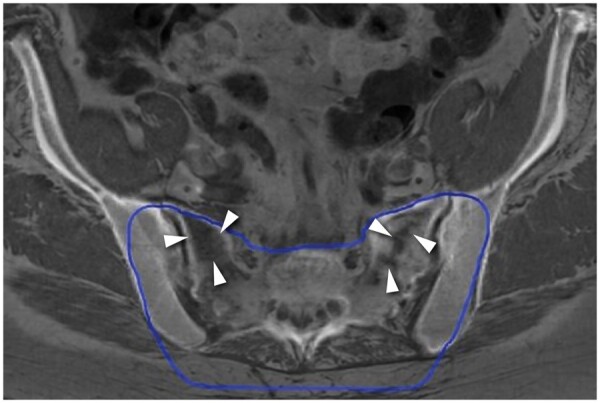

Methods: Clinical data, including details of all surgical procedures and radiotherapies of patients histologically diagnosed with sacral chordoma between 2008 and 2023 available at our database, were retrospectively reviewed. Inclusion criteria were as follows: availability of diagnostic, treatment planning and follow-up magnetic resonance and/or computed tomography scans, and completed treatment. Scans were re-evaluated for the presence and location of IF defined as linear abnormalities with(out) bone marrow oedema (BME)-like changes.

Results: From 48 included patients (29 male, median age 66, range 27-85), 22 were diagnosed with 56 IF (45.8%). IF occurred 3-266 months following the treatment. All sacral and iliac bone IF had vertical components parallel to the SI joint. Twenty patients had bilateral and 16 unilateral IF. BME-like changes were visible in 46 IF (82.1%, 0.80, P ≤ .001). In 13/56 IF (23.2%), BME-like changes were seen prior to IF diagnosis; in only 1 patient, BME-like changes did not develop into an IF. Thirty-nine IF (84.7%) occurred within low-dose volume and 7 (15.3%) outside of irradiated volume in 16/44 irradiated patients. Six IF occurred in 1 patient treated with surgery only.